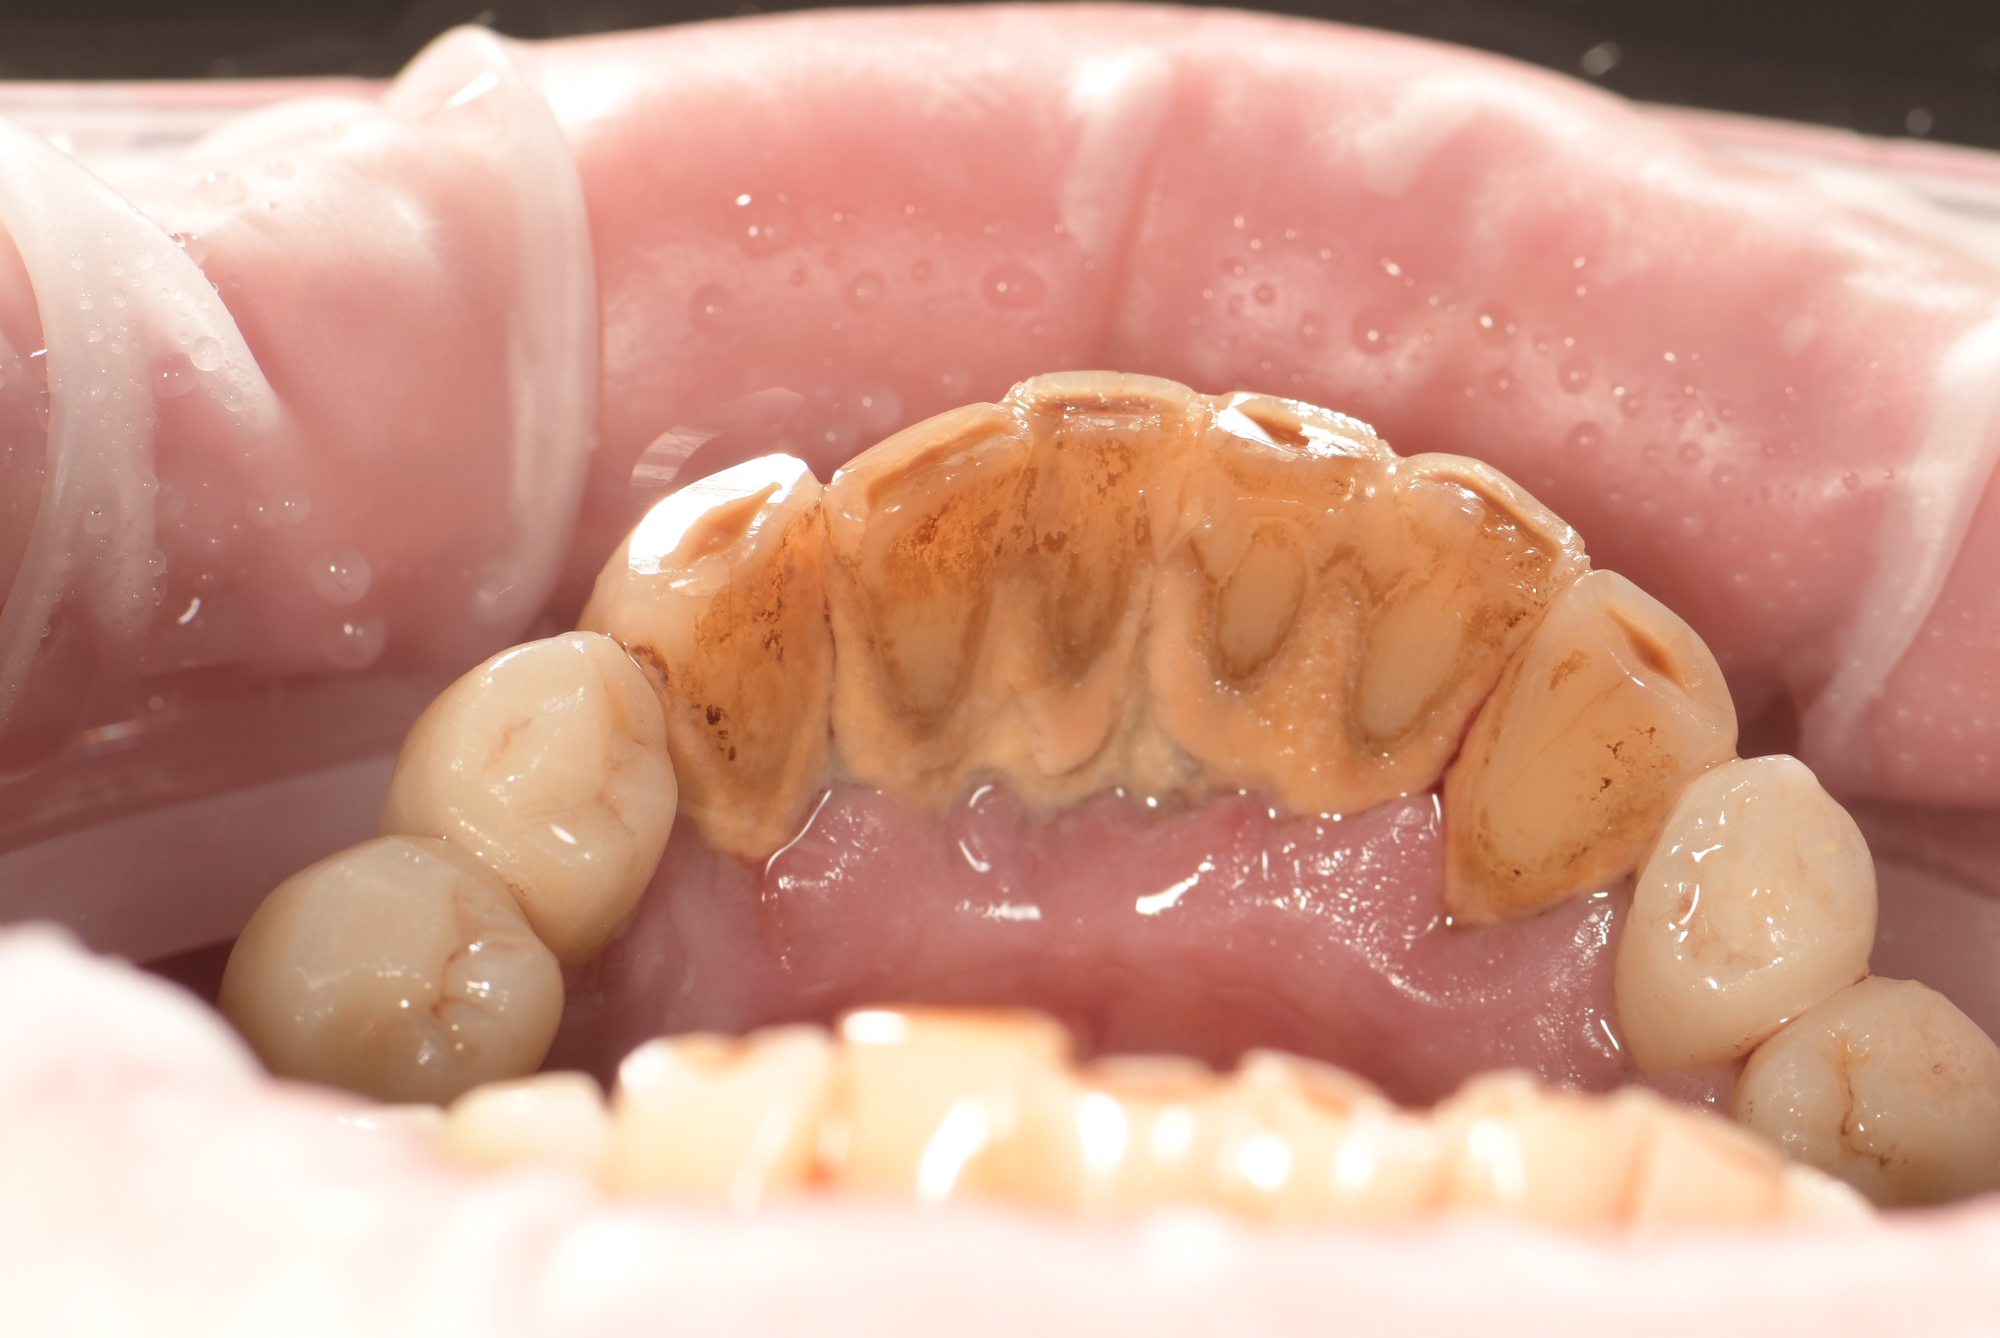

До

Професійне чищення зубів

Професійне чищення зубів дає прекрасні результати, так як дозволяє не тільки зняти зубні відкладення, але й відполірувати зубні поверхні. Мікробам і харчовим забрудненням складніше прикріплятися до гладкої емалі, тому після процедури швидкість накопичення нальоту на зубах знижується.

Чищення зубів ультразвуком або іншим спеціальним приладом позбавляє від затверділого нальоту - зубного каменю. У домашніх умовах неможливо зняти зубний камінь, не пошкодивши емалеву поверхню зубних одиниць.

Професійне чищення зубів, ліквідуються максимум мікробів, має не менше значення, ніж точна діагностика стоматологічних захворювань та їх якісне лікування. Зубний наліт є основним джерелом шкідливих мікроорганізмів в порожнині рота та головною причиною появи стоматологічних проблем. Чим більше нальоту накопичується на зубах, тим вразливіші стають ясна та зубні тканини. Чищення зубів у стоматолога - захід профілактичний, а потім вже естетичний.